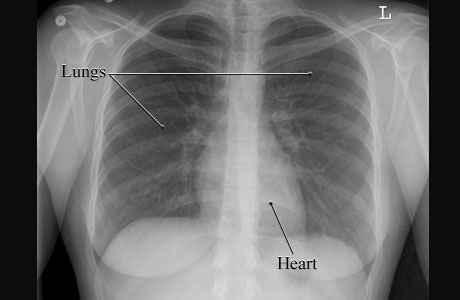

Image of a normal chest

This is a picture of a normal chest X-ray of a woman showing the air-filled spaces of the lungs and the more solid grey shape of the heart. The lungs and heart are normal in size and shape.